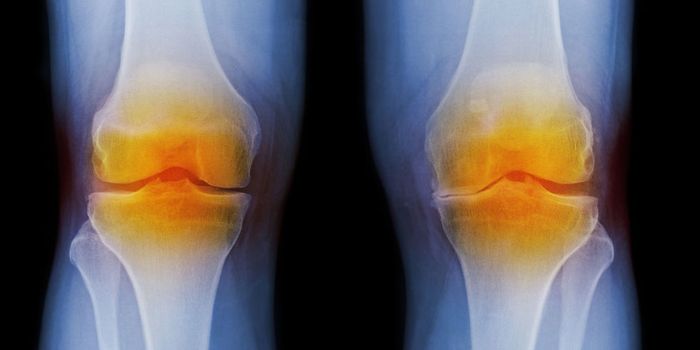

JUN 19, 2018Clinical & Molecular DXThere is a new way to diagnose arthritis and watch its progression slowly over time to determine the best route of treat ...

APR 30, 2024Clinical & Molecular DXIn osteoarthritis, the tissues that cushion joints begin to degenerate, leading to stiffness, pain, and swelling. Accord ...

APR 19, 2017Cell & Molecular BiologyResearchers found that a common ingredient in many junk foods may be directly contributing to osteoarthritic joint degen ...